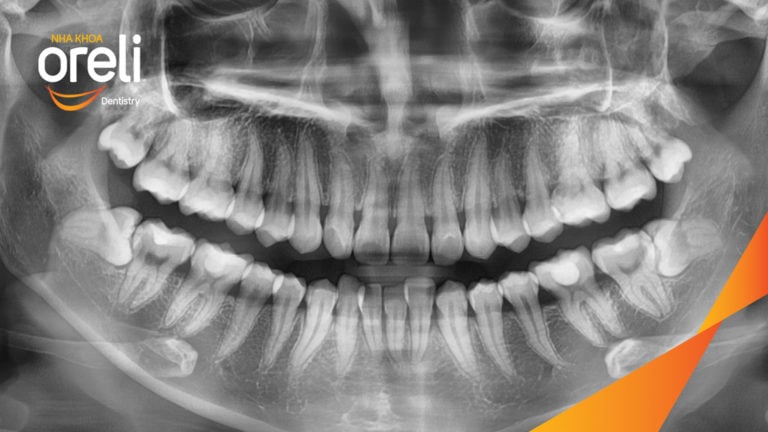

Ca niềng chỉnh chen chúc hẹp hàm nặng cả trên và dưới – Kết quả điều trị thực tế tại nha khoa Oreli Niềng răngChen chúc Xem thêm